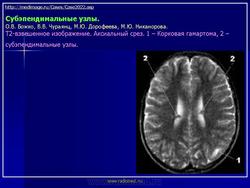

Факоматозы. Туберозный склероз, или синдром Бурневиля - Прингля 1. +

Туберозный склероз, или синдром Бурневиля - Прингля.

Туберозный склероз (болезнь Бурневилля-Прингла, синдром Бурневилля - Брессау) - глиоз белого вещества мозга, проявляющийся в раннем детстве эпилептическими припадками (в 85%), олигофренией в сочетании с нараста­ющей пирамидной и экстрапирамидной симптоматикой, кожной патологией. В возрасте 4-6 лет на лице в форме бабочки в области носа обычно появляют­ся множественные желто-розовые или коричнево-красные узелки диаметром чуть больше 1 мм - аденомы Прингла, которые обычно признаются аденомами сальных желез, однако есть мнение и о том, что они представляют собой про­исходящую из нервных элементов кожи гамартрому.

На поверхности мозга наблюдаются единичные или множественные глиома-тозные узлы, по цвету несколько светлее окружающего мозга и плотнее его на ошупь, возможна их кальцификация. Узлы могут быть и в белом веществе, под­корковых ганглиях, а также в стволе мозга и в мозжечке.

Встречаются и аномалии развития извилин мозга в виде микро- и пахигирии. Заболевание чаще носит спорадический характер. Бляшки достигают диаметра 5-20 мм. В коре больших полушарий и мозжечка иногда могут быть обнару­жены пластинчатые тельца, напоминающие амилоид. Происходит дегенерация клеток коры. При КТ-исследовании головы нередко можно выявить кальцифика-ты и глиальные узелки в паравентрикулярной области, субэпендимарно вдоль на­ружных стенок боковых желудочков, в зоне межжелудочкового отверстия Мон­ро, реже - в мозговой паренхиме. На М РТ головного мозга в 60% выявляются гипотеденсивные очаги в одной или обеих затылочных долях, которые расце­ниваются как участки неправильной миелинизации (Козлов А.В., 2002).